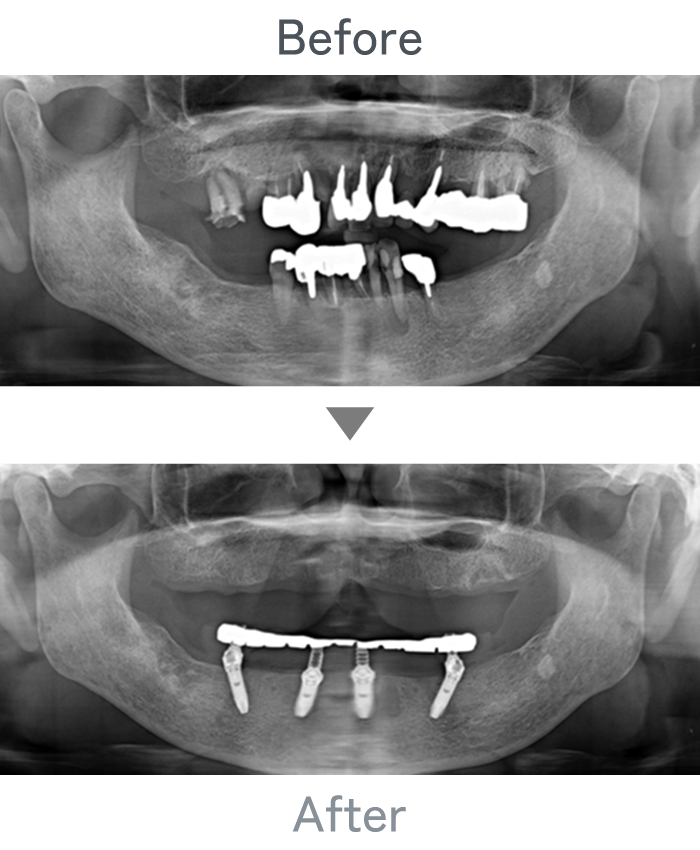

All-on-4

+

金属床義歯

主訴 入れ歯が使えなくて固定式にしたい

治療法 上顎:金属床義歯

下顎:All-on-4

治療期間 4ヶ月

※仮歯は手術当日に装着

費用 ・上顎金属床義歯:200,000円

・下顎All-on-4:2,500,000円

小 計:2,700,000円

消費税:270,000円

合 計:2,970,000円

※インプラント体、上部構造ともに『10年保証』

副作用

• メンテナンスが必要